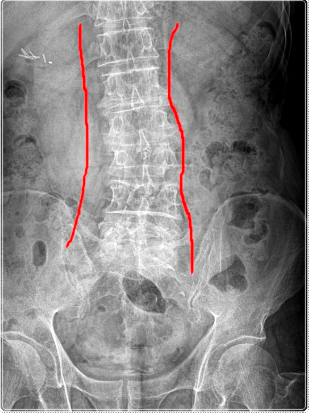

연산동체형교정은 단순히 외관을 바로잡는 과정이 아니라, 발-골반-척추-어깨로 이어지는 체형의 연결고리를 이해하는 과정입니다.